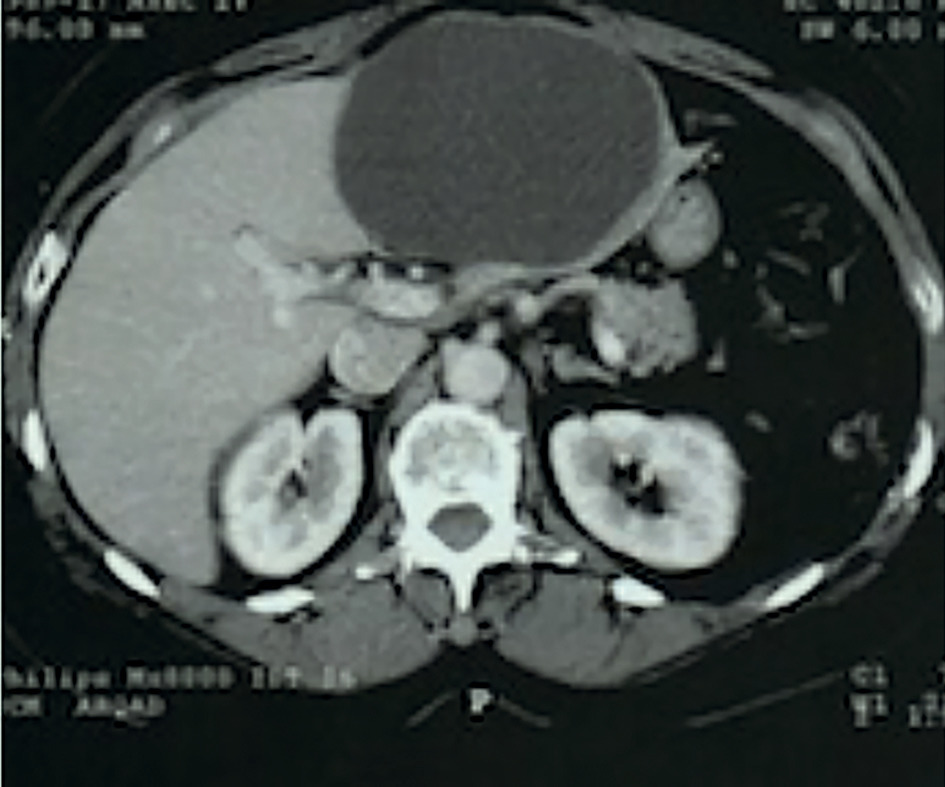

Cette masse augmentant rapidement, avec intensification des douleurs et apparition d’une gêne à l’inspiration, un scanner abdominal avec injection est demandé en urgence. Il confirme un volumineux kyste liquidien occupant tout le segment hépatique n° III (fig. 2 ).

Cette masse augmentant rapidement, avec intensification des douleurs et apparition d’une gêne à l’inspiration, un scanner abdominal avec injection est demandé en urgence. Il confirme un volumineux kyste liquidien occupant tout le segment hépatique n° III (

L’intervention chirurgicale sous vidéo-laparoscopie, faite 15 jours plus tard, a découvert un kyste biliaire de 10 cm sur-infecté, confirmé par l’analyse histologique. La résection du segment hépatique n° III a été nécessaire pour cette patiente.